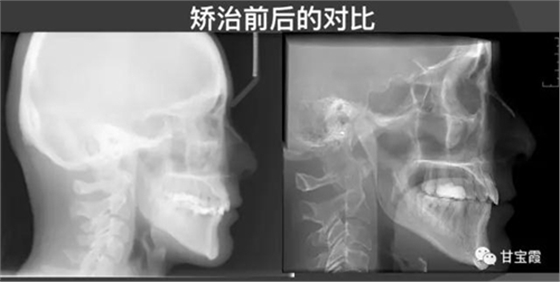

下圖是矯正前后的開(kāi)口頜像的對(duì)比,患者朋友看到這么好的治療效果,很后悔幾年前做的烤瓷修復(fù),還白白的磨了好牙。

所以這個(gè)病例告訴我們,如果你想鑲牙,一定先想到正畸醫(yī)生是否能幫助你關(guān)閉缺牙間隙,以免后悔呦。